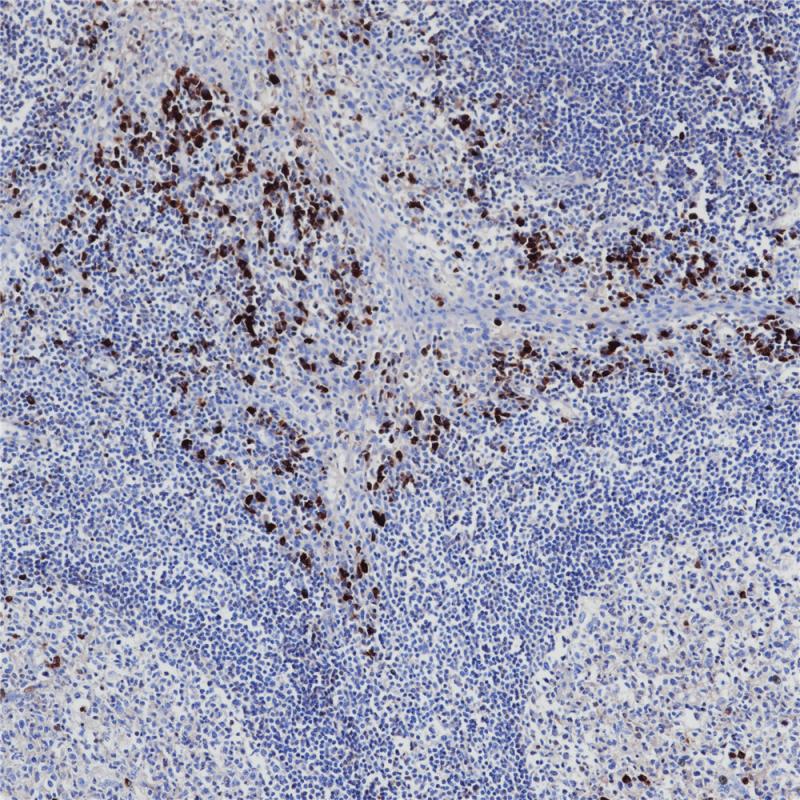

IgA 重组兔单克隆抗体

阳性对照

扁桃体